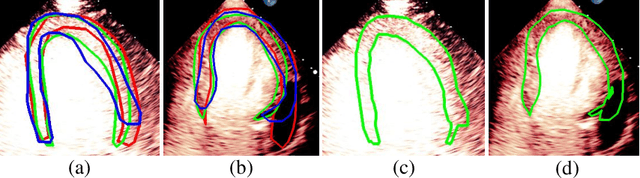

Abstract:Most existing deep learning-based frameworks for image segmentation assume that a unique ground truth is known and can be used for performance evaluation. This is true for many applications, but not all. Myocardial segmentation of Myocardial Contrast Echocardiography (MCE), a critical task in automatic myocardial perfusion analysis, is an example. Due to the low resolution and serious artifacts in MCE data, annotations from different cardiologists can vary significantly, and it is hard to tell which one is the best. In this case, how can we find a good way to evaluate segmentation performance and how do we train the neural network? In this paper, we address the first problem by proposing a new extended Dice to effectively evaluate the segmentation performance when multiple accepted ground truth is available. Then based on our proposed metric, we solve the second problem by further incorporating the new metric into a loss function that enables neural networks to flexibly learn general features of myocardium. Experiment results on our clinical MCE data set demonstrate that the neural network trained with the proposed loss function outperforms those existing ones that try to obtain a unique ground truth from multiple annotations, both quantitatively and qualitatively. Finally, our grading study shows that using extended Dice as an evaluation metric can better identify segmentation results that need manual correction compared with using Dice.